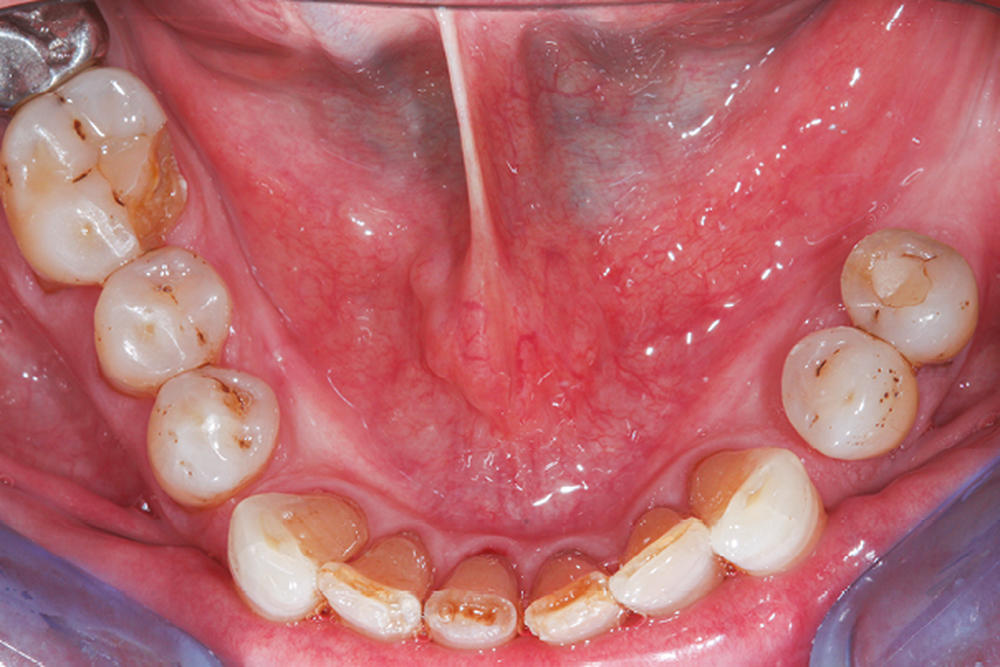

La perte d’une ou plusieurs dents entraîne la perte des points de contact, responsables de la stabilité et de la continuité de l’arcade. Par conséquent, une avulsion a pour première conséquence la migration ou la version d’une ou plusieurs dents distales (fig. 1 et 2). Cela est vrai en antérieur comme en postérieur.

Cette version, quand elle se produit, modifie les espaces interdentaires et complique l’hygiène proximale des patients. Des caries peuvent alors se développer en interproximal sans que cela soit forcément visible à l’examen visuel (fig. 3 et 4). Les radios de type bite-wing (rétro-coronaires) prennent alors tout leur sens (fig. 5 et 6).